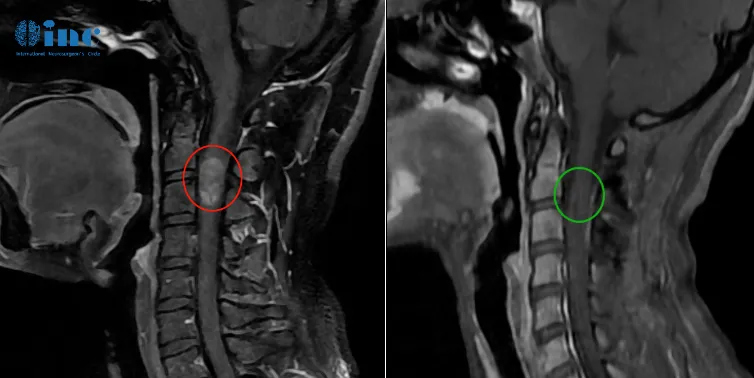

33歲的鄭女士2016年因晨起頸部疼痛和自感右上肢無(wú)力,提示頸椎椎管占位性病變,期間鄭女士因?yàn)閼言形葱腥魏沃委?。然?021年前患者感到癥狀加重,肢體出現(xiàn)無(wú)力及麻木以及溫度異常。2022年8月行核磁復(fù)查,病變較2017年范圍明顯增大,累及延髓和顱頸交界區(qū),且向下方延伸到整個(gè)頸部脊髓以及一直到第一胸椎水平,病變累及范圍近15cm。為了更好的陪伴著孩子的成長(zhǎng),鄭女士決定尋求世界大咖的治療……

▼巴教授術(shù)前術(shù)后影像對(duì)比

巴教授術(shù)前術(shù)后影像對(duì)比圖片

巴教授評(píng)估回復(fù):

“當(dāng)然,病人需要手術(shù)治療,而且應(yīng)該在腫瘤比現(xiàn)在小的時(shí)候更早接受手術(shù)。但是,正如我從視頻中看到的,由于病人的神經(jīng)功能狀態(tài)相當(dāng)好,手術(shù)還是可行的,也是必要的。”

2022年11月巴教授疑難示范手術(shù)期間,2022年11月23日,這臺(tái)長(zhǎng)達(dá)12個(gè)小時(shí)的高難度手術(shù)在蘇州獨(dú)墅湖醫(yī)院順利完成,手術(shù)時(shí)長(zhǎng)相當(dāng)于兩臺(tái)手術(shù)——延髓和脊隨髓內(nèi)。

術(shù)后第12天查房,鄭女士已經(jīng)可以正常下地站立,肢體活動(dòng)正常,除了右手稍微無(wú)力,術(shù)后3個(gè)月,在鄭女士傳來(lái)的康復(fù)視頻里,她已經(jīng)可以正常行走,術(shù)后無(wú)力的右手已經(jīng)也可以正常抓握小物體、手部運(yùn)動(dòng)正常。